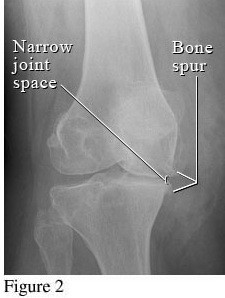

Hình ảnh so sánh giữa khớp bình thường và khớp bị thoái hóa khớp gối

Để phân biệt các giai đoạn của bệnh thoái hóa khớp gối, cần dựa vào phim X- quang theo tiêu chuẩn chẩn đoán thoái hoá khớp của Kellgren và Lawrence như sau:

Hình ảnh của khớp gối trên phim X-quang: Khe khớp hẹp rõ, nhiều gai xương kích thước vừa, đặc xương dưới sụn, đầu xương có thể bị biến dạng.

Hình ảnh của khớp gối trên phim X-quang: Khe khớp hẹp nhiều, gai xương có kích thước lớn, đặc xương dưới sụn, đầu xương biến dạng rõ.